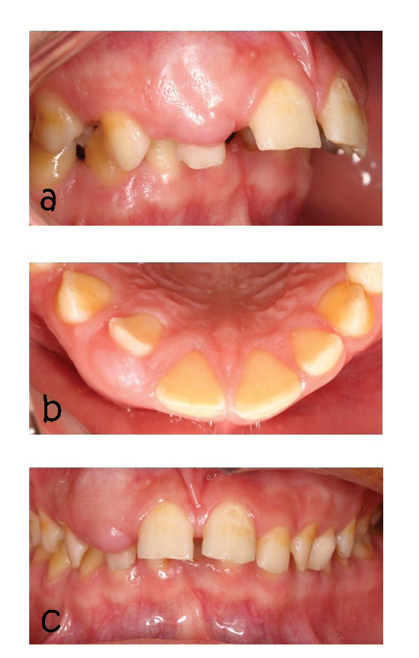

We describe a case of a 15-year-old boy of Asian descent, who had a lump in the lateral maxillary incisor region with dimensions of approximately 0.3*0.8*0.8*0.3 cm, which is unusual for AOT cases in terms of the position of the affected tooth and the sex of the person involved (Figure-1). Maxillary lateral incisor tooth drift was seen (Figure-1). The mucosa above the mass was normal and did not cause pain, paresthesia, or infection. The lymph nodes were not palpable. The patient and his family members did not report a history of systemic medical problems. The patient had no history of trauma, and no asymmetry was observed in the extraoral view. The patient’s occlusion was based on Angel classification, class 2, subgroup 2 (Figure-1).

Figure 1. a: Intraoral photograph (lateral view), b: Intraoral photograph occlusal view showing shift lateral incisor palatal aspect ,c: Intraoral photograph with obliteration vestibular